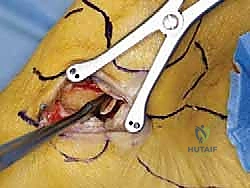

الخطوة الثالثة: الشق الجراحي والوصول الآمن

يتم عمل شق جراحي دقيق ومدروس على الجانب الداخلي للكاحل، خلف وتحت الكعب الإنسي. يستخدم الدكتور هطيف تقنيات تشريحية دقيقة لحماية الهياكل الحيوية المحيطة، وخاصة العصب الصافن (Saphenous Nerve) والوريد المرافق له، لتجنب أي تنميل أو ألم عصبي مزمن بعد الجراحة.

الخطوة الرابعة: تقييم وإصلاح رباط الدالية (Repair vs. Reconstruction)

بمجرد الوصول إلى رباط الدالية، يتم تقييم درجة التلف:

* الإصلاح المباشر (Direct Repair): إذا كانت أنسجة الرباط الممزقة ذات جودة جيدة (عادة في الإصابات الحديثة)، يقوم الدكتور هطيف بخياطتها مباشرة. يستخدم خطاطيف تثبيت عظمية (Suture Anchors) صغيرة جداً ومصنوعة من مواد متوافقة حيوياً (تذوب مع الوقت أو من التيتانيوم) لغرس الخيوط القوية في عظمة الكعب الإنسي، ثم يتم سحب الرباط الممزق وتثبيته بقوة في مكانه التشريحي الأصلي.